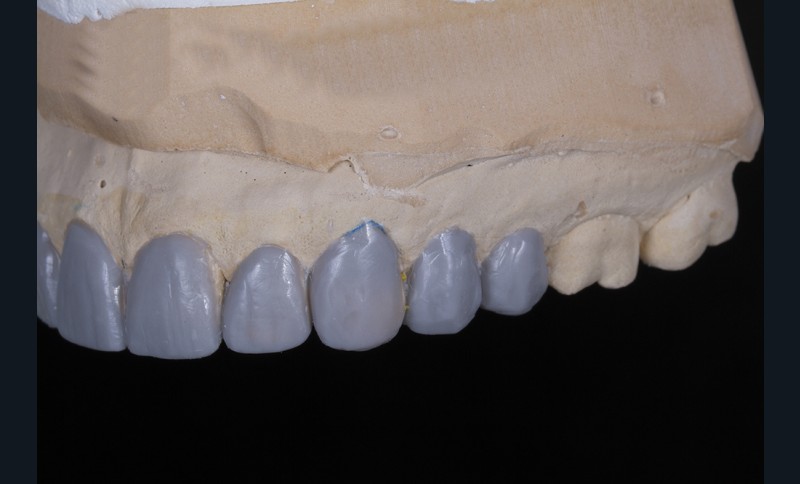

Dans un deuxième temps, un wax-up global permet de restaurer les courbes d’occlusion. Il est à noter que la présence d’égressions dentaires, faute d’antagoniste ou d’anciennes restaurations prothétiques inadaptées, crée des usures inégales au sein de la cavité buccale. Aussi, la présence de zones non recouvertes par le wax-up dans les secteurs postérieurs est courante, permettant ainsi la préservation de zones amélaires majeures pour le collage (fig. 2).